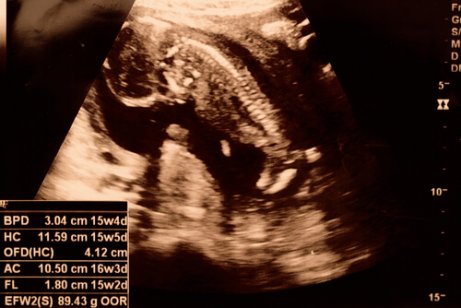

In some ultrasound images, it’s possible to determine the baby’s sex as early as 15 weeks. Furthermore, the fetus’s arms and legs are growing, and can flex his or her joints.

During week 15, the baby’s skeleton hasn’t formed yet. However, you can see his dorsal spine and its nerve endings. Furthermore, the fetus can raise his neck and hands. In fact, in some cases you can even observe the baby putting his fingers in his mouth.